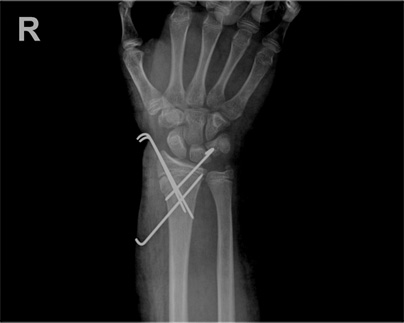

x-ray 사진

소아 손목 골절 수술 전

소아 손목 골절 수술 후